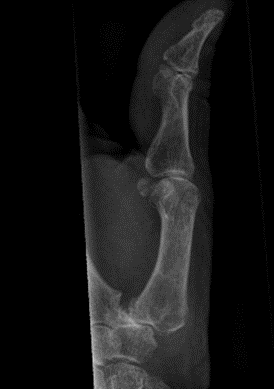

X-ray showing subluxation, joint space narrowing, sclerosis and osteophytes, with a Robert’s view on the right

An X-ray can be used to confirm the diagnosis. Views of the base of the thumb, including a PA, lateral, and Robert’s view (hyper-pronated) should be done. This will show subluxation of the carpometacarpal joints (CMCJs), with joint space narrowing, sclerosis, osteophytes and cysts.